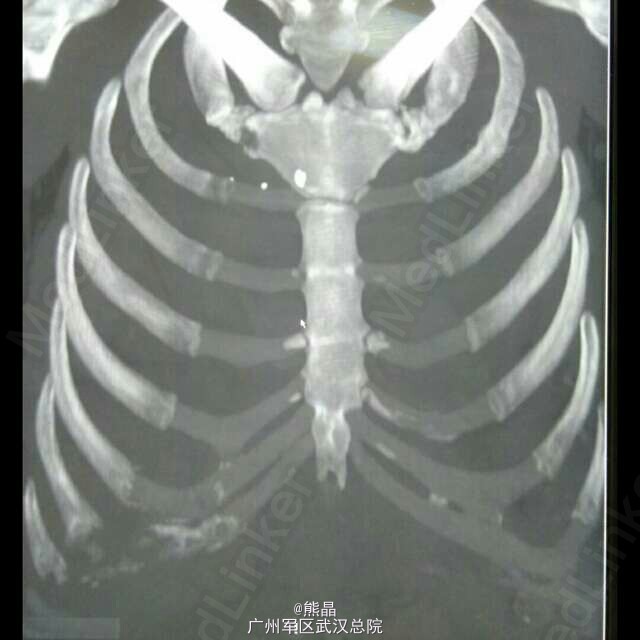

肋软骨脓肿

病史:患者男性,38岁,半年前出现右侧胸部疼痛,逐渐加重。 CT三维重建提示右第7、8肋软骨炎伴肋骨部分坏死溶解。